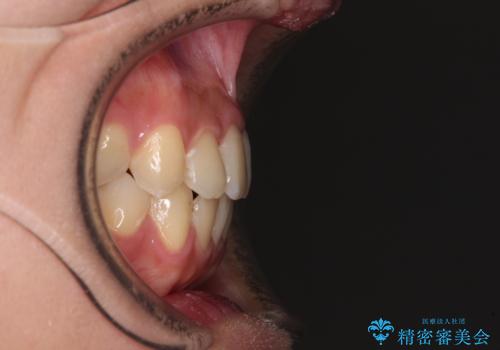

前歯のクロスバイトを短期間で解消 目立たないワイヤー矯正

- 前歯のクロスバイトを治したいとのことで来院された患者様です。

できる限り楽して、短期間で治したいとのことで、ワイヤー装置にて矯正治療を行うこととしました。